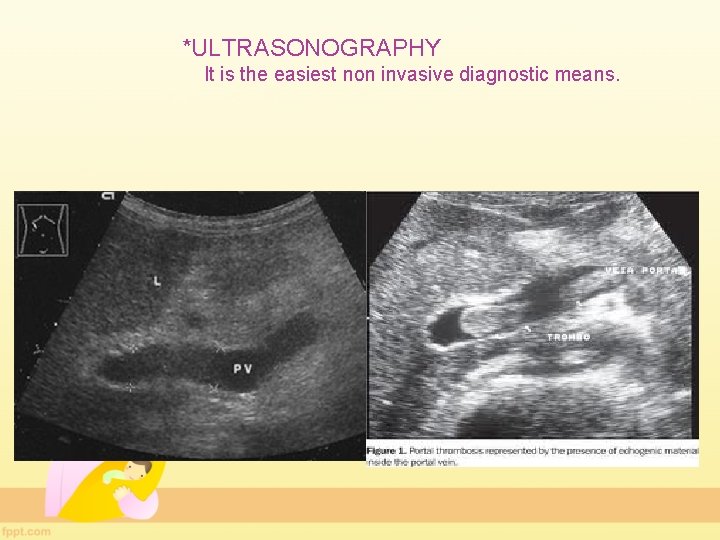

*ULTRASONOGRAPHY It is the easiest non invasive diagnostic means.